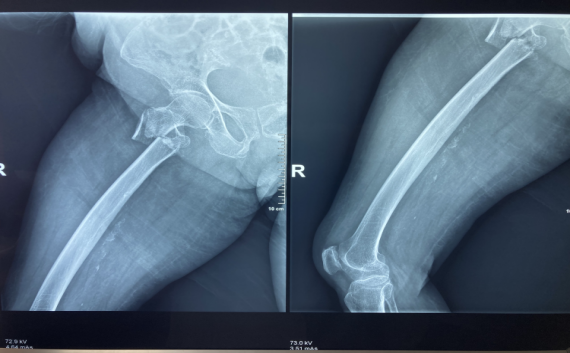

蔡奶奶今年98岁高寿,因“跌伤致右髋部疼痛伴活动受限5天。”到我院骨伤科治疗。入院后,被诊断为“右侧股骨粗隆间骨折”。

“虽然骨折手术并不复杂,但是蔡奶奶属于超高龄患者,各器官功能退化,心、肺功能下降,尤其是对手术的承受力下降、麻醉耐受力的降低、术后感染、康复及一系列并发症,每一道都是难关。”副院长张有文详细介绍,如果保守治疗,蔡奶奶需长期卧床,也容易引发肺部感染、褥疮、深静脉血栓等一系列的并发症,严重可导致生命危险。

面对如此特殊的病人,我院组织骨科、内科、麻醉科等多科专家讨论,最终制定出可行的手术及麻醉方案,并为术后并发症及康复治疗制定了周密的计划。

术中,麻醉科医生严格控制麻醉药品的剂量和浓度,密切观察病情,监测各项生理指标,确保老人的生命体征平稳。副院长张有文为百岁老人实施了右股骨粗隆间骨折闭合复位髓内钉内固定术,历时40分钟,手术圆满完成。